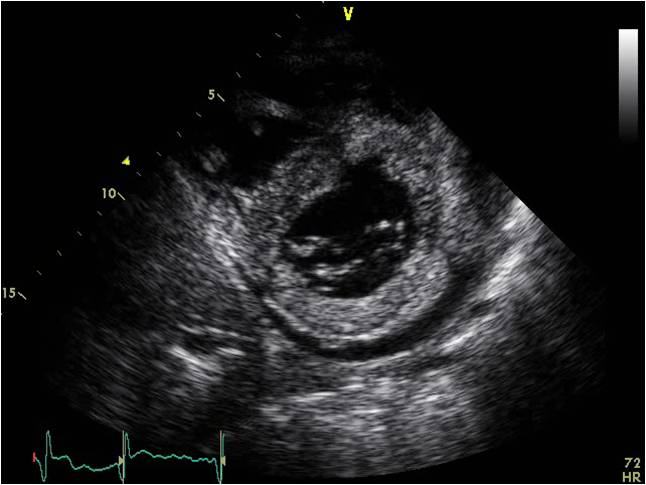

心脏淀粉样变 ECHO:LVH,室壁回声增强,可见颗粒状回声,二尖瓣主动脉瓣增厚,少量心包积液。

心脏淀粉样变 ECHO:LVH,室壁回声增强,可见颗粒状回声, 心包积液。

限制型心肌病ECHO:双房大;右室心尖部闭锁